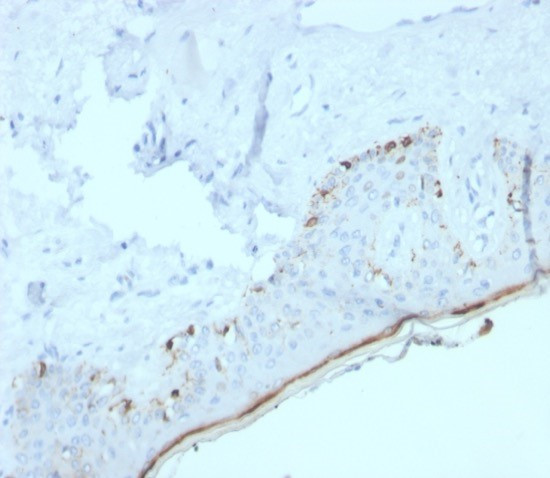

MART-1/Melan-A/MLANA (Melanoma Marker) Antibody in Immunohistochemistry (Paraffin) (IHC (P))

MART-1/Melan-A/MLANA (Melanoma Marker) Antibody (2315-RBM14-P1ABX) in IHC (P)

Formalin-fixed, paraffin-embedded human skin stained with MART-1 Recombinant Rabbit Monoclonal Antibody (MLANA/4385R). HIER: Tris/EDTA, pH9.0, 45 min. 2 °: HRP-polymer, 30 min. DAB, 5 min. {{ $ctrl.currentElement.advancedVerification.fullName }} 验证信息 View more